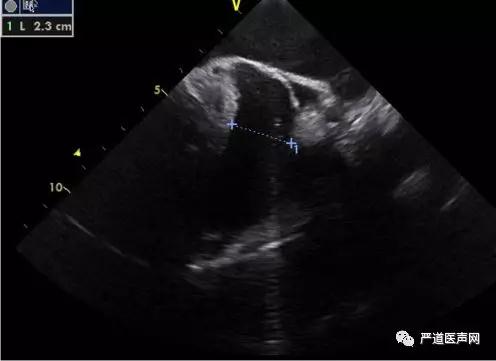

在TEE术前检查中,分别需要0°,45°,90°,135°的多角度评估,对应ICE,通常在左房中部(mid-LA),可以观察到左心耳短轴开口,此时相当于0-45°的TEE视野, 相对容易实现;当探头位于左房底部时,在此基础上倾斜180°,可观察到左心耳长轴开口,相当于90-135°的TEE视野,这里需要一定的经验积累和导管操作微调,具体主要操作介绍如下。

0°-探头置于mid-LA时,再推送1cm左右,邻近左上肺静脉口部偏后顶上区域,此时缓慢逆时针旋转直到可见主动脉短轴斜切面,此时左心耳开口;

45°-探头置于mid-LA时,可见二尖瓣的视野下,调节张力旋钮并轻微打P弯;

90°-也叫工作角度,当探头置于mid-LA并可见二尖瓣的视野下,缓慢推送在距离左上肺静脉口部1cm处适当调节张力旋钮并轻微打L弯;

135°-探头置于mid-LA时并可见二尖瓣的视野条件下,控制张力旋钮并打中度L弯。